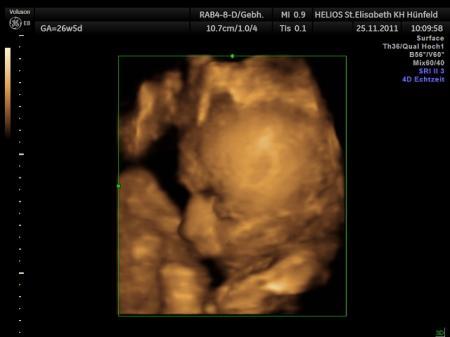

hallo ihr lieben zusammen ;-) also bei mir wurde in der 24 ssw festgestellt das unsere kleine maus wasser im kopf sammelt und im nierenbereich. also niere löst sich mesitens wenn die kleinen da sind und pipi machen. uns wurde dann gesagt das sich der wasserstau im kopf noch lösen kann, da jeden tag sich das gehirn weiterentwickelt und wächst und wir in der 30 ssw zur kontrolle wiederkommen sollten(6. Wochen warten des grauens) nun gut, dann sind wir wieder in der 30ssw dagewesen und die nachricht war nicht ganz so erfreulich. leider hat sich der wasserstau nicht gelöst und uns wurde gesagt das der maximale grenzwert bei 10 liegen würde. Unsere kleine maus hat im linken kopfbereich 10,5 und im rechten 10,9 und wir sollen in der 36.ssw erneut kommen(wieder schreckliche 6 wochen warten) kennt sich jemand damit aus oder kennt jemanden damit? wie schlimm sind die werte wirklich? müssen wir uns doch mehr sorgen machen als wir denken? es ist mein erstes Baby und hab absolut keine erfahrung und mach mir natürlich schreckliche gedanken. ich glaub die ärtze verschönen das etwas um mich nicht noch mehr zu beunruhigen. danke euch schonmal. GLG und eine restliche tolle komplikationslose SCHWANGERSCHAFT!!!!